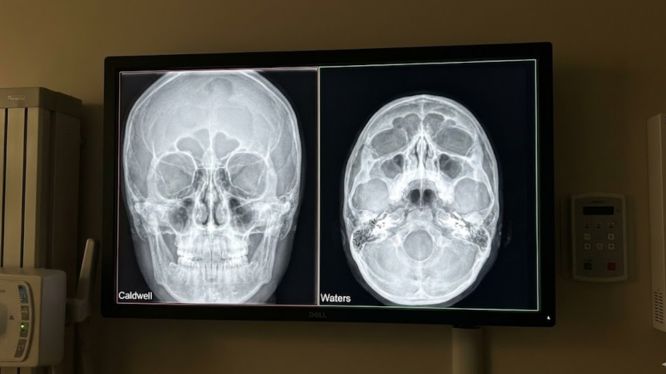

Por lo tanto, hoy te explicamos de forma clara, detallada y visual la comparación de proyecciones Caldwell vs Waters. Además, conocerás sus usos clínicos, qué anatomía se observa en cada una y cuándo elegir cada proyección, especialmente en odontología, cirugía maxilofacial y estudios de senos paranasales.

También conocida como proyección posteroanterior (PA) con angulación cefálica, la radiografía Caldwell,, es una técnica radiográfica diseñada para evaluar principalmente el cráneo anterior y los senos paranasales, con énfasis en estructuras superiores.

🔍 ¿Qué estructuras se observan mejor en la radiografía Caldwell?

La radiografía Caldwell es ideal para visualizar:

✔️ Senos frontales

✔️ Porción anterior del cráneo

✔️ Órbitas (bordes superiores)

✔️ Hueso frontal

✔️ Etmoides anteriores

Por eso, es muy utilizada en estudios de senos paranasales y evaluación de patologías óseas 🦴.

🌊 ¿Qué es la proyección Waters?

Además, la proyección Waters, también llamada proyección occipitomentoniana, está diseñada para mostrar con mayor claridad las estructuras medias e inferiores del rostro, especialmente los senos maxilares.

🔍 ¿Qué se observa mejor en la proyección Waters?

También, la proyección Waters permite evaluar con mayor precisión:

✔️ Senos maxilares

✔️ Piso de las órbitas

✔️ Huesos cigomáticos

✔️ Maxilar superior

✔️ Cavidades nasales

Por eso es una de las favoritas en odontología y cirugía maxilofacial 😷🦷.

🧠 1. Diferencias en la anatomía visualizada

| Aspecto | Radiografía Caldwell ⭐ | Proyección Waters 🌊 |

|---|---|---|

| Senos frontales | Excelente | Limitada |

| Senos maxilares | Parcial | Excelente |

| Órbitas | Bordes superiores | Piso orbitario |

| Maxilar superior | Menor detalle | Alta definición |

| Etmoides | Anteriores | Menor énfasis |